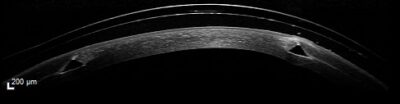

Anpassung einer Freiformsklerallinse bei einem Keratokonus Grad 2

Aufgrund der Unverträglichkeit von kleinen formstabilen Keratokonuskontaktlinsen erfolgte die Anpassung von Sklerallinsen in Freiform-Technologie. Wie auf den Schnittbildern des Vorderabschnitt-OCTs zu sehen ist, liegt der Randbereich harmonisch auf der Sklera bzw. Bindehaut auf. Daher können die Linsen täglich 15 Stunden getragen werden. Die Linsen wurden mit 72 peripheren Linsen-Rand-Sektoren für das Auge gefertigt.